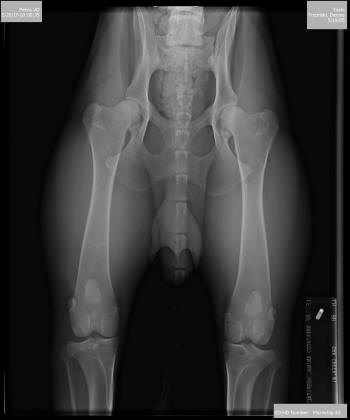

•  OFA certified Good at almost 5 years of Age!